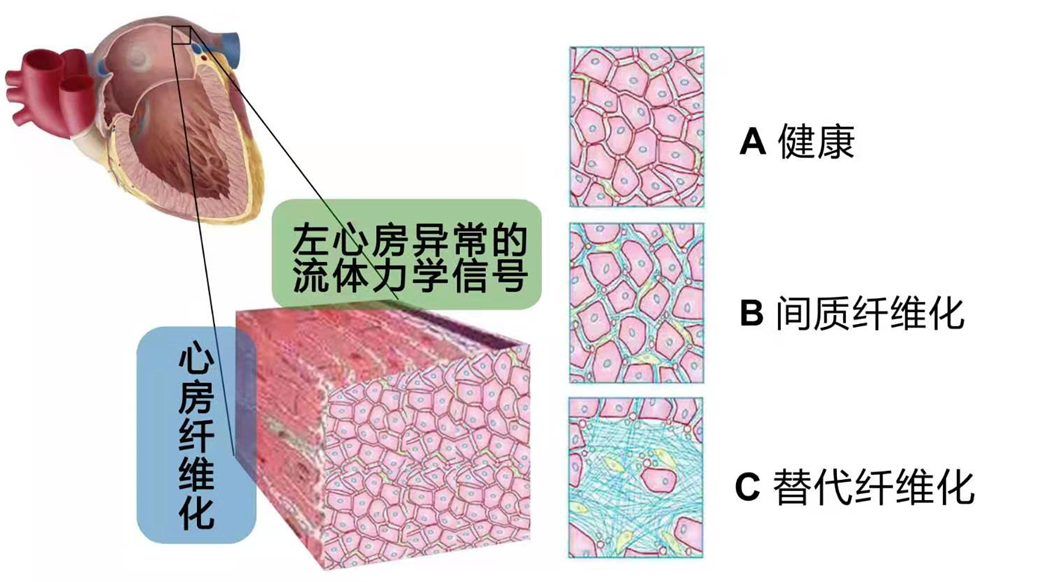

研究表明,心房纤维化被认为是心房重构的重要标志,主要因为在心肌组织中,凋亡的心肌细胞死亡后不能再生新细胞,相反,成纤维细胞会增殖以填补空隙。邻近心肌间质纤维化部位的瘢痕形成,可阻止心肌修复,并易发生心律失常。心房肌组织不同程度的纤维化是心房结构重构最突出的改变特点。(如图2)

图2 左心房异常的流体力学信号导致心房纤维化的发生,A健康状态,B间质纤维化状态,C 替代纤维化状态。